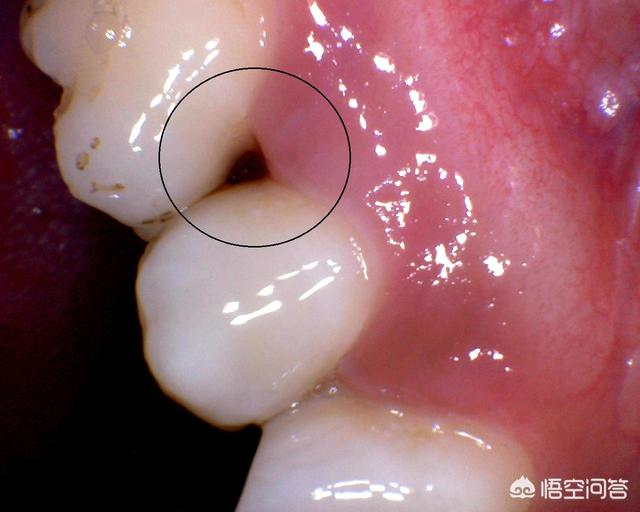

标记的地方就是智齿去第二磨牙之间塞东西。这种问题可以选择直接拔出智齿从而彻底解决嵌塞食物问题!

像这种临面龋坏导致的问题,可以通过树脂修复或者是成人可选择做全冠修复解决 等